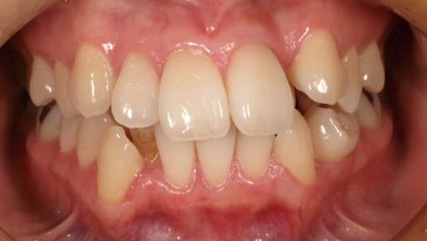

治療前

治療終了前

乱ぐい歯、でこぼこがとても酷い状態になります。歯が前後的に重なってしまっている、八重歯になっているなどがこのジャンルに入ります。

顎の大きさと歯の大きさのギャップが大きく、時には歯を抜かないと矯正治療ができない場合もあります。当院では治療期間が長くなるが抜かない治療方針など、一つの治療プランだけでなく、さまざまな可能性の治療方針を説明させて頂くよう心掛けております。こういった考え方はインフォームド・チョイスと言われ近年大切にされている考え方と言われております。